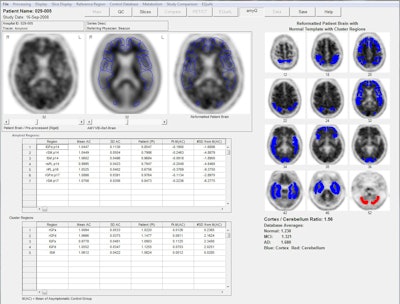

To quantify brain activity, the researchers utilized the NeuroQ software to calculate standardized regions of interest, measuring activity in 240 different regions of the brain and then clustering them into 47 different volumes. The software then produces a report with the subject's original brain scan, a template brain image with regions of interest outlined, and the metabolism in the posterior regions of the brain illustrated in 2D color.

Syntermed's NeuroQ software can analyze and quantify the distribution of FDG and amyloid PET tracers in individual scans. This screen shot demonstrates uptake of an amyloid agent. Image courtesy of Syntermed.

The software helped determine the DPI for regions of the brain adversely affected by Alzheimer's, such as the bilateral and posterior cingulate cortex and the bilateral temporal cortex, and compare the findings to regions of the brain not influenced by dementia.